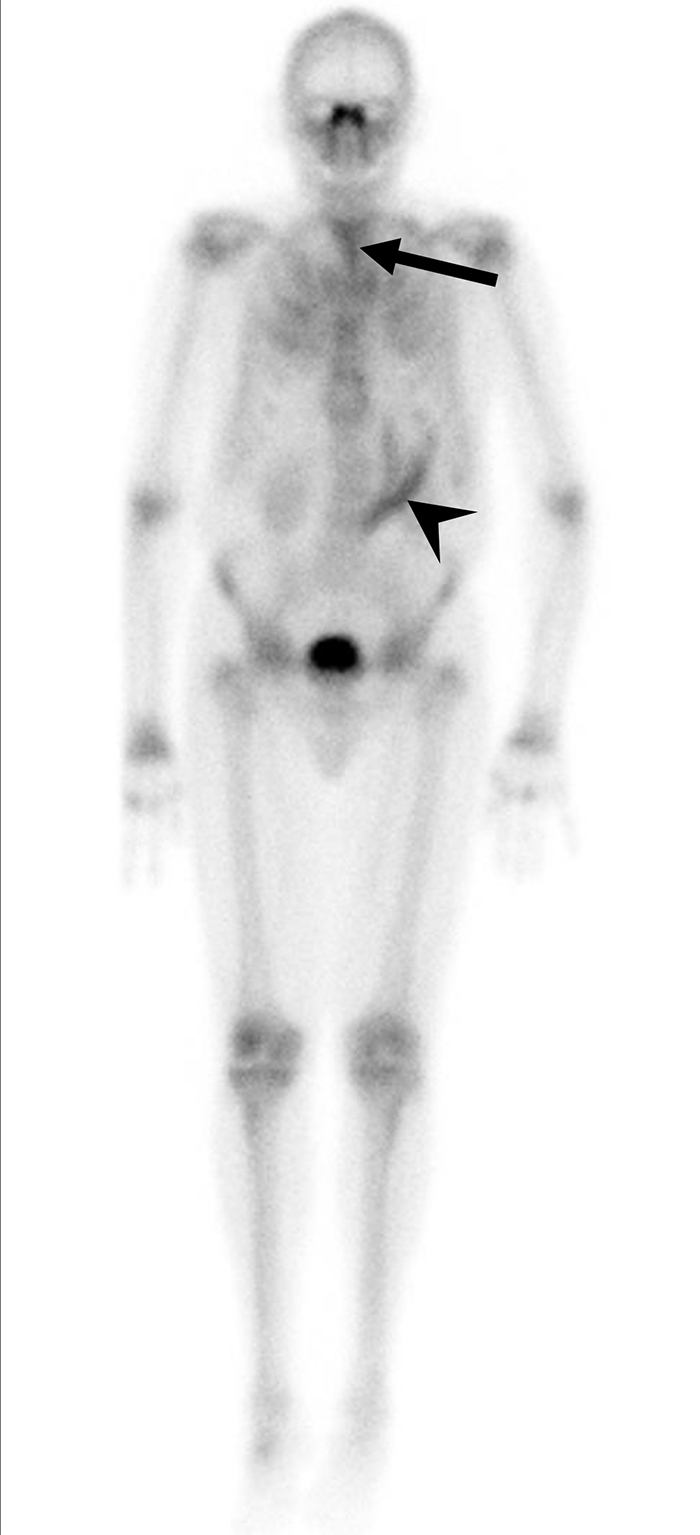

Uomo di 35 anni con lombalgia in peggioramento da 6 mesi e recente insorgenza di dolore alla spalla sinistra, associati a inappetenza e malessere. È stata eseguita una scintigrafia ossea trifasica con 99mTc-MDP.

La fase di flusso ha mostrato un’ipervascolarizzazione a livello delle vertebre L3-L4 (a). Le immagini statiche di blood-pool (b. 1) e tardive (b. 2) della regione lombare hanno evidenziato un aumentato accumulo ematico e una captazione tardiva del tracciante nella medesima regione a livello L3-L4. L’immagine whole-body di blood-pool (c) e le immagini tardive (d) acquisite dopo 3 ore hanno mostrato un’aumentata captazione a livello delle vertebre L3-L4, dell’articolazione sterno-claveare sinistra e del manubrio dello sterno. Le immagini SPECT-TC della vertebra L4 (e) hanno rivelato una lesione distruttiva con interessamento dei tessuti molli pre- e paravertebrali; reperti simili di distruzione e raccolta fluida sono stati notati nell’articolazione sterno-claveare sinistra (f). Nella lesione vertebrale si osserva un sequestro a bottone (freccia nera). La RM eseguita 2 giorni dopo ha confermato una spondilodiscite.